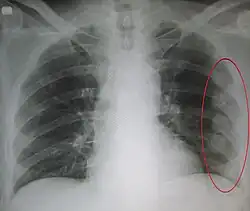

An X ray showing multiple old fractured ribs of the person's left side as marked by the oval

Plain X-rays often pick up displaced fractures but often miss undisplaced fractures.[13] CT scanning is generally able to pick up both types of fractures.[13]